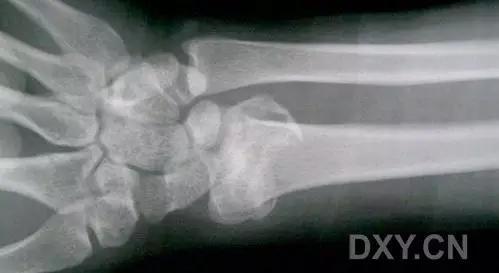

3. Smith 骨折

桡骨远端骨折伴骨折远端向掌侧移位,也称为反 Colles 骨折。

来源:radiology assistant